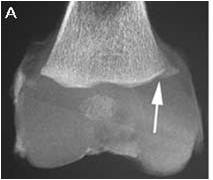

Fractura en Asa de cubo

Niño de 7 semanas Rayos X del espécimen